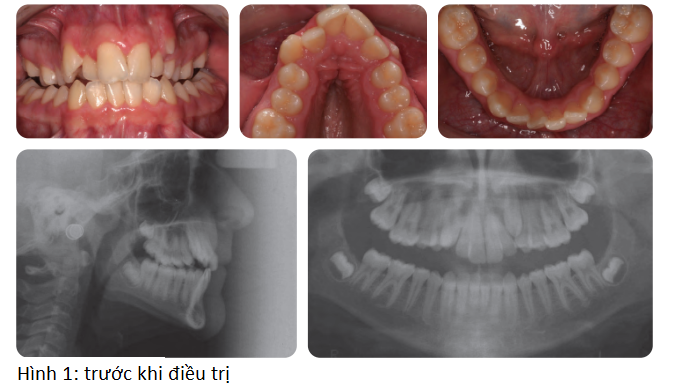

Bệnh nhân nam 14 tuổi có sai khớp cắn hạng I trên nền xương loại II trung bình với tăng kích thước dọc phức tạp bởi chen chúc nặng cung hàm trên, các răng nanh hàm trên lệch ngoài, cắn chéo răng sau 2 bên và độ cắn trùm giảm (hình 1)